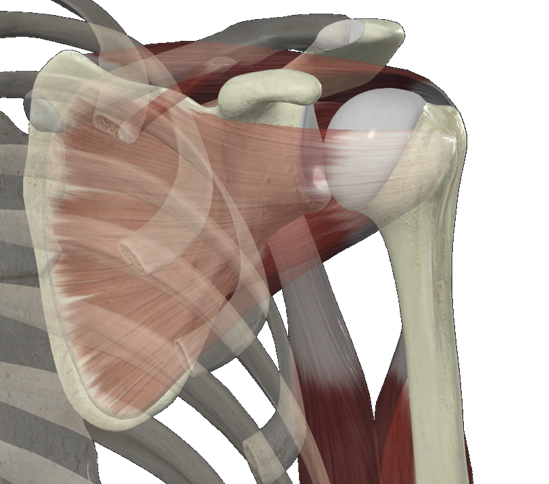

3 어깨질환

- 어깨관절은 몸의 힘을 팔로, 팔의 힘을 몸으로 전달해줍니다.

- 회전근개 힘줄들은 어깨의 넓은 움직임을 만듦과 동시에 구조적 안정성을 유지해주기 위해 애쓰는 구조물입니다.

- 팔은 어깨관절을 통해 몸통에 붙기 전에 견갑골과 먼저 만나고(견갑상완관절) 견갑골이 흉곽과 만납니다(견봉쇄골관절, 견흉관절).

- 따라서, 유연하고 튼튼한 견갑골을 회복하기 위하여 ’견갑골 안정화 운동’이 회전근개 손상 재활에 참 중요합니다.